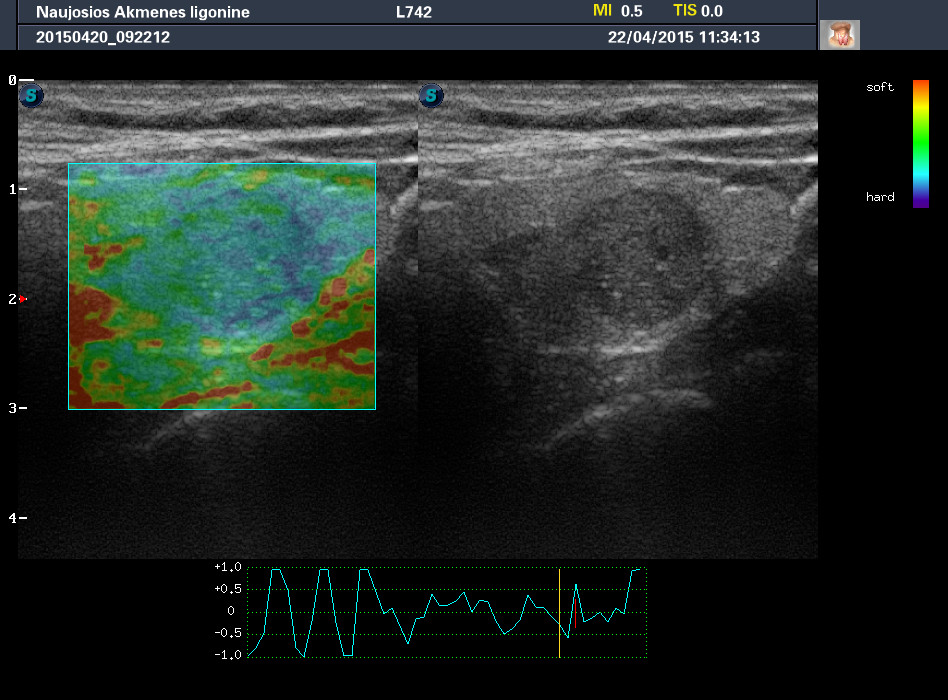

Случай 2

Женщина 61 год, жалоб нет. Рост узла за год +1 мм. Регионарные ЛУ не увеличены.

apr222015113257_27.jpg

phpBB [video]

1-й узел злокачественный, а 2-й ,скорее всего, доброкачественный. Но,понятное дело, нужна пункция и было бы здорово узнать результат.

Mattiola писал(а): И,простите, что за исследование на сканах, не на видео? Я такого не делаю и,к сожалению, не знаю,как интерпретировать его(

Эластография. http://www.medison.ru/si/art380.htm